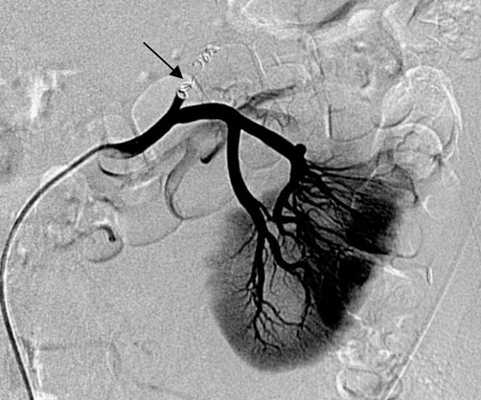

Эмболизация - это малоинвазивная эндоваскулярная процедура, направленная на прицельную закупорку сосудов, которые снабжают кровью пораженные ткани. Проводится эмболизация почки под тщательным рентгенологическим контролем с помощью тонкого катетера, в большинстве случаев он вводится в кровеносный сосуд, питающий больную почку, в области паха. В сосуд подается контрастное вещество, которое хорошо видно на рентгене. Таким образом определяется локация ветви сосудов, по которым кровь поступает в пораженный орган. Далее через катетер вводятся эмболы (клейкие вещества, вызывающие закупорку) до того момента, пока он не будет отрезан от кровотока.

Ангиография

Ангиография - это инвазивный, но более точный метод определения месторасположения и степени сужения или закупорки просвета сосуда. Через небольшой катетер, проведённый к почечным сосудам вводится контрастное вещество. С помощью рентгеновских лучей получают изображение сосудов на экране. Само контрастное вещество выделяется через почки, что иногда может повлиять на их функцию. Это требует осмысленного подхода, особенно у лиц с нарушением функции почек. Очень важно отметить, что в современных условиях часто есть возможность устранить сужение прямо при проведении ангиографического исследования с помощью специальных баллонов и стентов - устройств, удерживающих сосуды в расширенном состоянии.

Это сравнительно новые, но многообещающие методы лечения сужения сосудов, в частности почечных. Как уже упоминалось, процедура может быть выполнена во время ангиографического исследования. Для этого через маленькие проколы на бедре или в подмышечной области проводятся специальные катетеры к Вашим почечным артериям. На конце катетера находится крошечный баллончик. При раздувании его в месте сужения сосуда, происходит раздавливание атеросклеротической бляшки и прижатие её к стенке артерии, таким образом, расширяя суженный участок. Эта процедура называется баллонной ангиопластикой. Часто для закрепления эффекта и сохранения просвета в расширенном состоянии ангиопластика может быть дополнена стентированием - постановкой специального металлического устройства, стента, в суженный участок артерии.